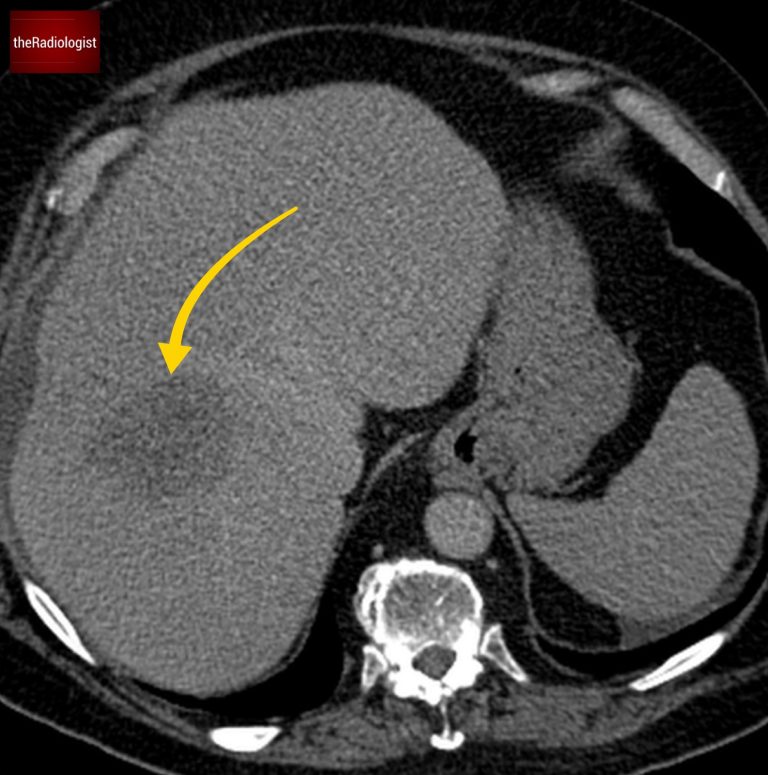

CT scan

Now have a look through the CT of the abdomen and pelvis. This is post IV contrast in a portovenous phase. I know you want to get going but you may need to wait a few seconds for the scan to load. Tap the first icon on the left to scroll.

CT scan findings

When we look at the CT we will see diffusely dilated large bowel loops. The key here is to see whether we can find a transition point, ie is there a point where the dilated large bowel becomes collapsed.

If we follow the sigmoid colon down we will find some mural thickening and a transition point suggesting mechanical large bowel obstruction. The differential at this point lies between a malignant stricture and a benign diverticular stricture.

If we follow the colon round from the caecum we will find a transition from dilated colon to collapsed sigmoid colon. At this point there is some mural thickening. Now what are the causes of large bowel obstruction? The list is long but the most common and the most serious cause is colonic carcinoma (compare with this with small bowel obstruction where the majority of the time the aetiology is non-malignant). Other more common causes of large bowel obstruction include diverticular disease and sigmoid volvulus.

Going back to our case, with mural thickening within the sigmoid colon we have to flag that this is a possible colon cancer. What makes us more certain is the presence of low density ill defined liver lesions which represent liver metastases. Note how these do not show fluid density and are not well defined as you would expect with simple liver cysts.

There is a large ill defined low density lesion within the liver suggestive of a liver metastasis.